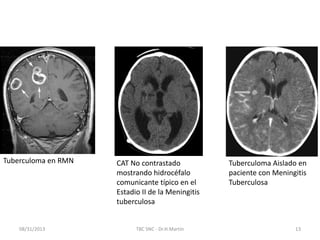

Tuberculoma de

localización en

tálamo derecho

08/31/2013 TBC SNC- Dr.H.Martín 14 Tuberculoma de localización en tálamo derecho